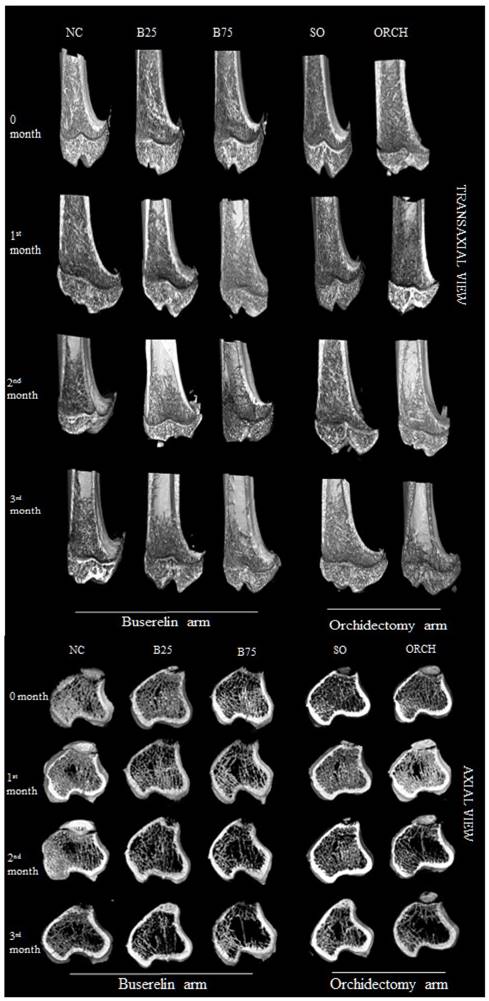

Figure 6 showed the three-dimensional (3D) reconstruction of trabecular and cortical bone at the proximal tibial metaphysis of male rats after three months of treatment. Trabecular bone was denser in the normal control group compared with the buserelin-treated groups, and in the sham-operated group compared with the orchidectomized group. Deterioration of trabecular bone was apparent for the orchidectomized, B75 and B25 group. Changes in cortical bone were not apparent among all the groups.

Figure 6

Three-dimensional micro-CT images of the trabecular microstructure of distal tibia metaphysis at the transaxial and axial view. Abbreviation: NC, normal group; B25, buserelin 25µg/kg groups; B75, buserelin 75µg/kg groups; ORCH, orchidectomy group; SO, sham orchidectomy group.